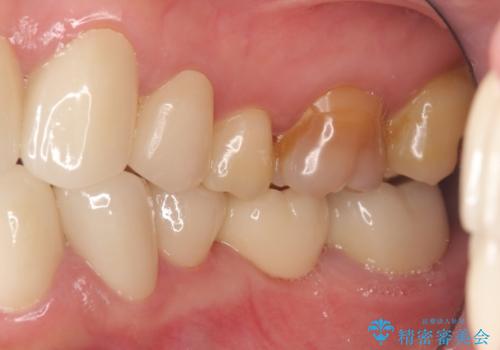

上顎は左側 4 番目から右側 4 番目までの 8 歯をオールセラミッククラウンで補綴しました。

下顎は左側 4 番目から右側 4 番目までの 8 歯と左下 567 ブリッジをオールセラミッククラウンで補綴し、右下67の銀歯はセラミックインレーによる修復を行いました。

今回用いたオールセラミッククラウンはジルコニアフレームという白い素材の上にセラミックを盛っているため、審美性が非常に高いのが特徴です。

また、ジルコニアは人工ダイヤモンドの材料にも使われているほど高い強度を持っており、そのためオールセラミッククラウンは審美性だけでなく、奥歯やブリッジの補綴も可能とするクラウンです。